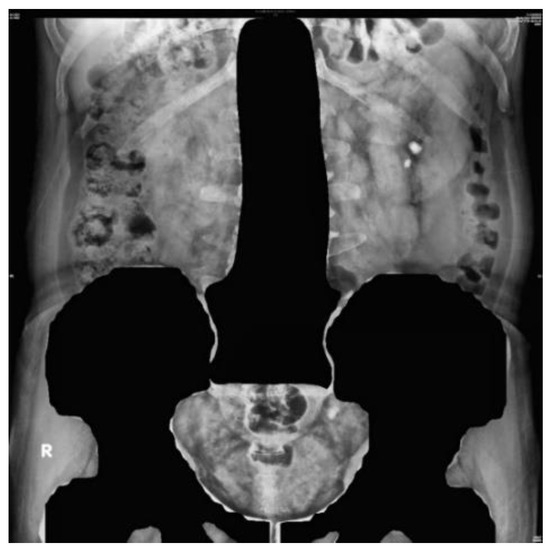

2.3.3. Image Cropping